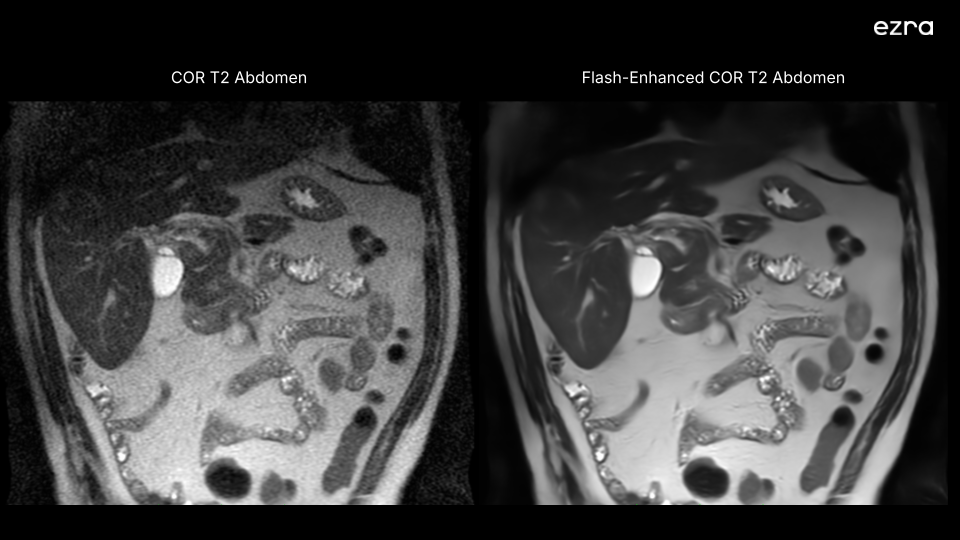

I'm excited to share that Ezra has received new FDA 510(k) clearance for a new version of our Ezra Flash AI. This clearance significantly expands our ability to enhance MR image quality, including the abdomen and pelvis, building upon our previous neuro imaging capabilities.

First, our Ezra Flash AI now delivers improved image quality by effectively reducing noise while preserving crucial diagnostic information across neuro, abdomen, and pelvis. This enhancement is particularly important for complex anatomical areas like the abdomen and pelvis, where clear imaging is essential for accurate screening.